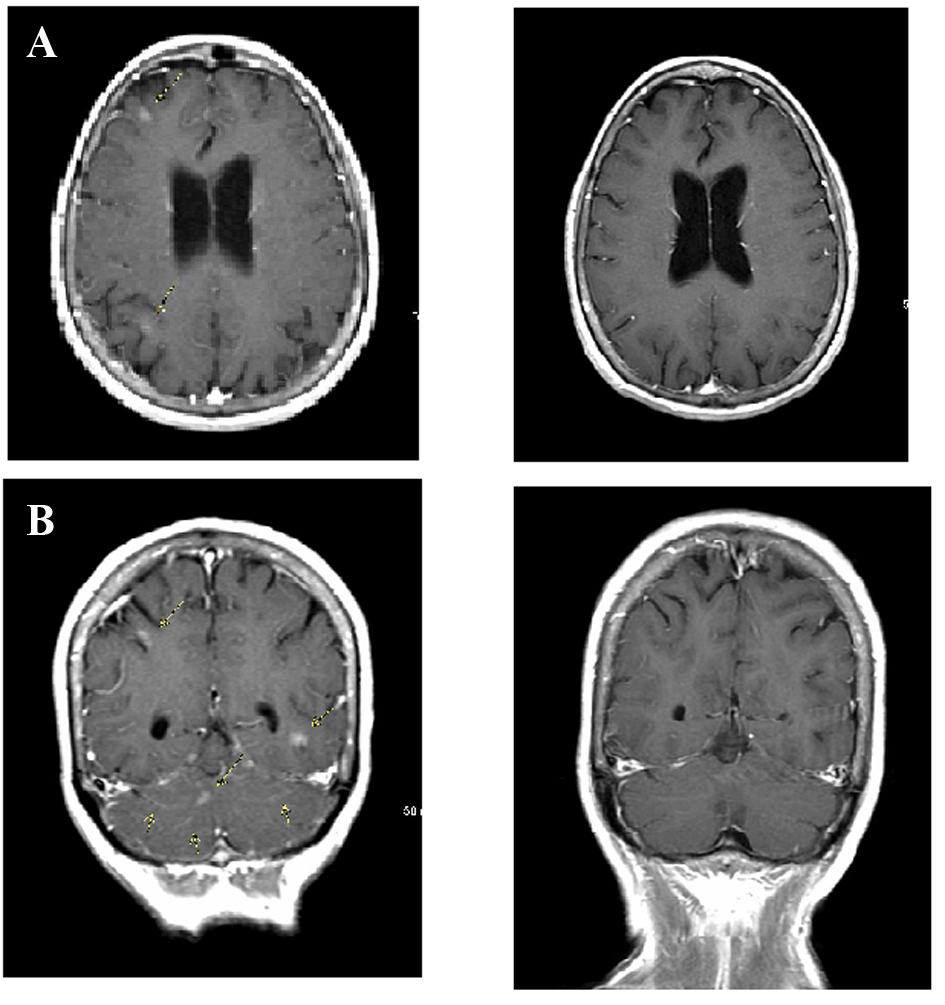

In July 2013, 18 months after diagnosis, the patient began experiencing episodes of confusion, headaches, bizarre sensations in the head and difficulties with short-term memory. An MRI of the brain showed patchy areas of leptomeningeal enhancement (Fig. 2A). A cerebrospinal fluid (CSF) study showed mild decrease in CSF glucose, normal protein level and the presence of multiple mononuclear cells consistent with adenocarcinoma. A CT-PET scan showed evidence of response to therapy with decrease in size of the lung mass to 6 mm without increased metabolic activity, resolution of pleural effusion and sclerosis of bone metastasis without increased metabolic activity.

![]() Click for large image | Figure 2. Leptomeningeal carcinomatosis. (A) Brain magnetic resonance imaging (MRI) obtained when patient first presented with neurologic deficits shows multiple sites of leptomeningeal enhancement on post-contrast T1-weighted sequences (arrows). (B) Following pulsed-dose erlotinib therapy, repeat MRI scan showed complete resolution of tumor. |

A diagnosis of LC was made and treatment options including intrathecal chemotherapy and cranial or craniospinal radiation were discussed. The patient refused these treatments mainly because of the death of her daughter who had LC related to an Ommaya reservoir for treatment of breast cancer several years ago. The patient was placed on pulsed erlotinib therapy with dose adjustments depending on toxicity. The patient derived her own optimal dosage of 600 to 750 mg daily for 3 days on and 2 days off resulting in a total dose of 2,550 mg per week. The patient noticed complete resolution of neurological symptoms in about a week and has remained symptom free at the time of this report more than 12 months after diagnosis of LC. The patient is symptomatic only in terms of grade 1 dermatologic toxicity and grade 1 diarrhea secondary to erlotinib. Results of spinal fluid analysis continue to show adenocarcinoma cells; however, multiple CSF samples failed to provide enough cells for molecular analysis.

CT-PET scan in March 2014 did not show any evidence of increased metabolic activity. Craniospinal MRI in April 2014 (Fig. 2B) did not show any evidence of metastatic disease or leptomeningeal enhancement.